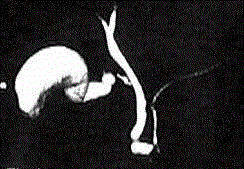

Figure 1. MRCP showing focal saccular dilation of the terminal part of the main pancreatic duct.